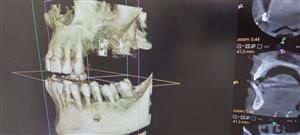

CT snimanje čeljusti (3D CBCT) u Dentalnom centru Centrodent u Rijeci predstavlja temelj suvremene dentalne dijagnostike i planiranja terapije.

Koristimo Carestream CS 8200 3D CBCT uređaj koji omogućuje visoku rezoluciju snimke uz kontroliranu i minimalnu dozu zračenja. Snimka pruža detaljan prikaz kosti čeljusti, zuba, korijena, sinusa i temporomandibularnih zglobova, što omogućuje preciznu procjenu stanja prije implantoloških, kirurških, endodontskih i ortodontskih zahvata.

3D analiza omogućuje točno planiranje terapije, smanjenje rizika i veću predvidljivost zahvata. Svaki nalaz tumači se stručno i individualno, uz jasne preporuke i transparentno objašnjenje daljnjih koraka.